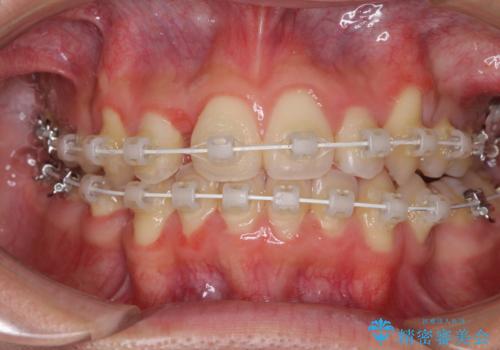

- 矯正装置

- 審美装置

- 上下の八重歯や乱杭歯を気にして来院され患者様です。

スペースを確保するため、上下左右の小臼歯を抜歯し、ワイヤー装置に矯正することとしました。

奥歯の咬み合わせの左右差が大きかったため、変則的な抜歯矯正を行いました。

治療期間はやや長期化しましたが、満足のいく歯並びとなりました。